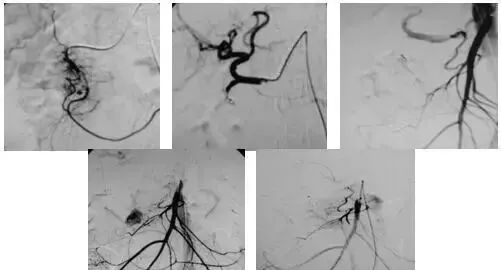

2、经导管血管栓塞法(Transcatheter embolization)

经原血管造影的导管或特制的导管,将栓塞物送至靶血管内,一是治疗内出血如外伤性脏器出血、溃疡病、肿瘤或原因未明的脏器出血。另一是用栓塞法治疗肿瘤,因肿瘤循环部分或全部被栓塞物阻断,以达控制肿瘤之生长,或作为手术切除的一种治疗手段;亦可用于非手术脏器切除,例如注射栓塞物质于脾动脉分支内,即部分性脾栓塞,以治疗脾功亢进,同时不影响脾脏的免疫功能。

(3)应用栓塞材料,钢圈,内支架治疗动脉瘤、AVM、动静脉瘘,血管性出血。

(1)选择性肿瘤供血动脉灌注化疗+栓塞治疗恶性肿瘤。

(3)应用栓塞术治疗海绵状血管瘤,蔓状血管瘤,子宫肌瘤,骨肉瘤,鼻咽部纤维血管瘤等。